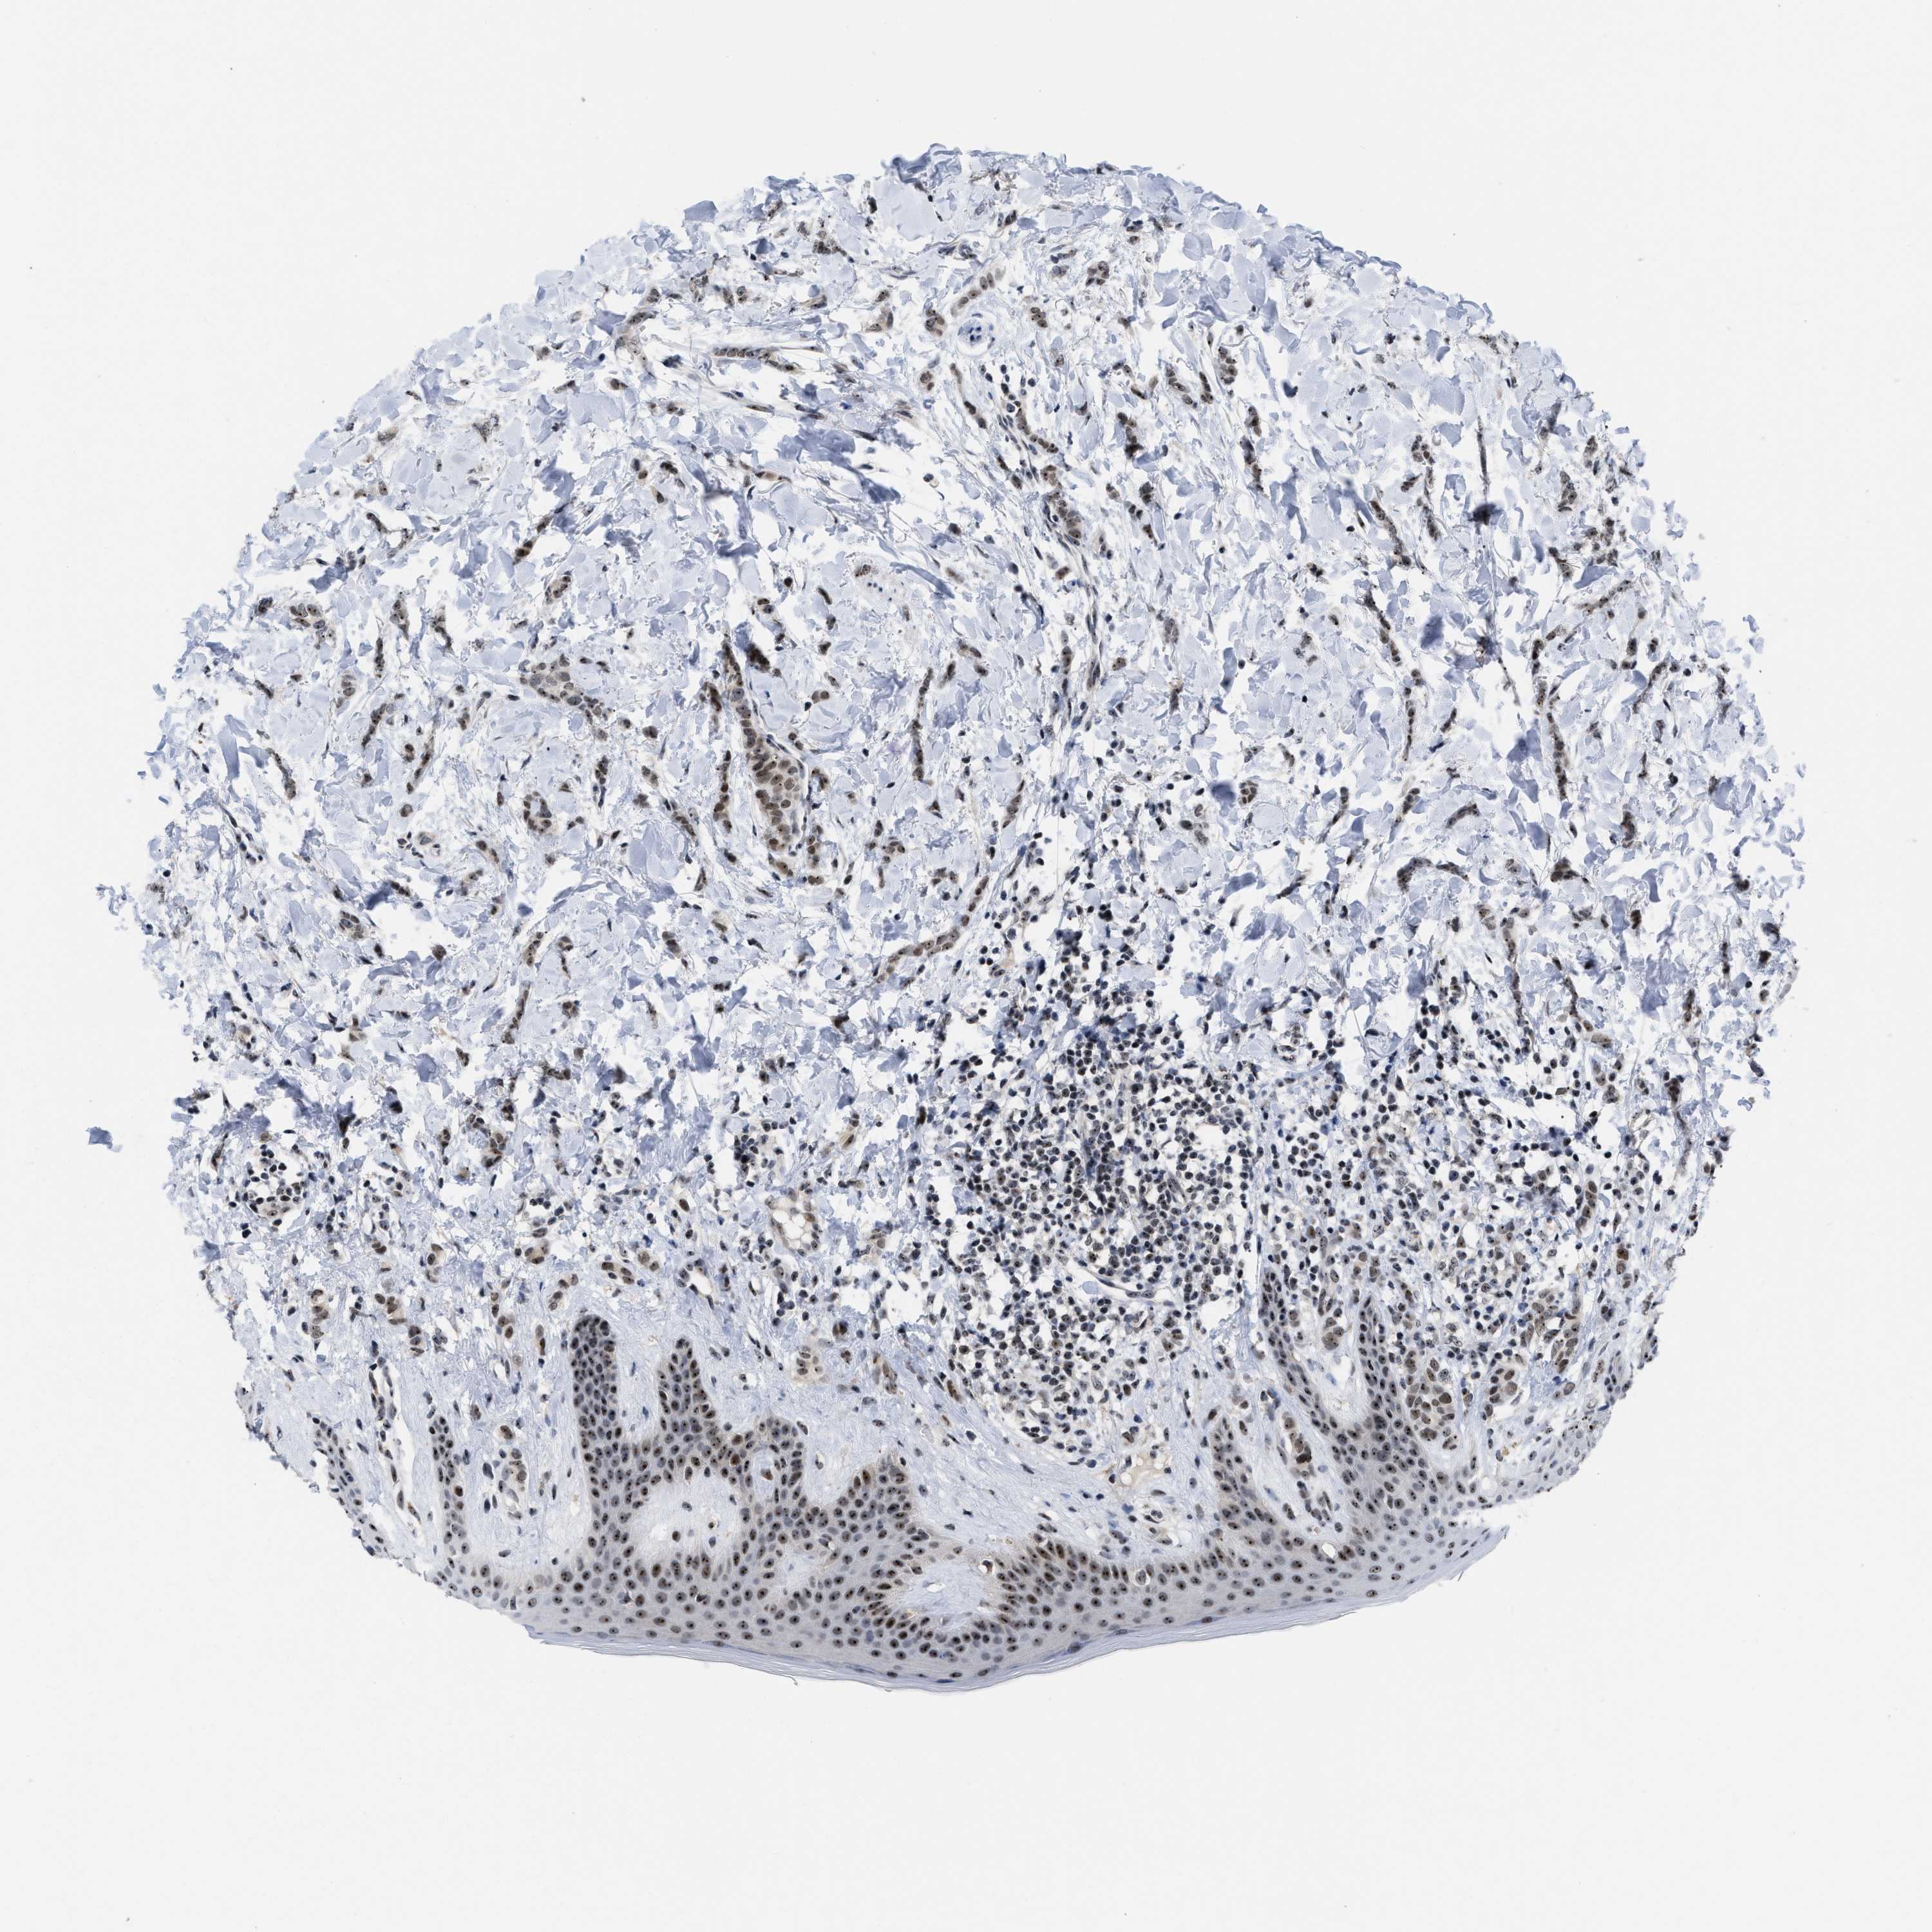

CANCER BREAST CANCER Show tissue menu

BRCA TCGA BRCA VALIDATION PROTEIN EXPRESSION